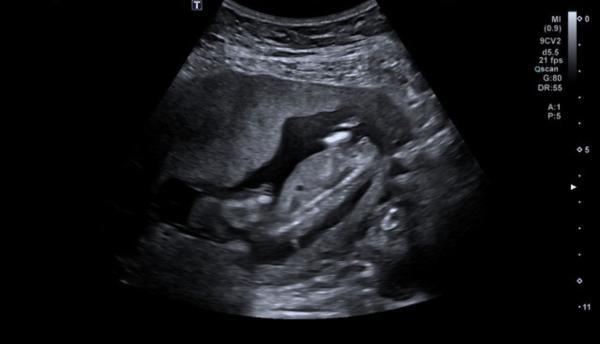

Hallo :) Ich bin aktuell in der 15. SSW und war vor wenigen Tagen bei dem Ersttrimesterscreening.  Mich würde interessieren, was ihr über das Geschlecht sagt, da meine Frauenärztin sich noch nicht ganz sicher war :) Natürlich ist es dann schwierig, hier das Geschlecht zu bestimmen aber neugierig bin ich trotzdem über Meinungen.  Wir würden uns über beides freuen und sind einfach zu ungeduldig, um noch 6 Wochen auf den nächsten Termin zu warten :) Ein NIPTtest wurde nicht gemacht, da es keine Indikation dafür gab.  Vielen Dank und liebe Grüße

Bild zu Vermutungen Jung oder Mädchen ? - Schwanger - wer noch? Rund um die Schwangerschaft

Junge